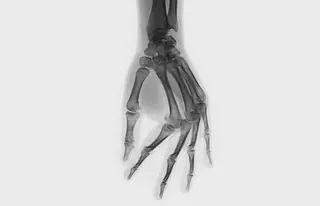

Существуют две гипотезы, объясняющие хруст в суставах. Первая предполагает, что независимо от излюбленной техники - дергаете ли вы палец или выкручиваете шею - происходит одно и то же: суставная капсула растягивается, ее объем увеличивается, а давление, наоборот, падает. Из-за этого суставная жидкость растекается, и в ней образуются пузырьки газа. Эти пузырьки лопаются с характерным звуком. Спустя 10-20 минут газы снова растворяются в жидкости - тогда можно хрустнуть еще раз. Согласно второй гипотезе, хруст возникает при движении из-за быстро натягивающихся связок и сухожилий. Когда капсула, сухожилия и связки растягиваются, сустав делается подвижнее, и человек чувствует комфорт. Ну а кому-то просто нравится звук.

Несколько исследовательских групп пытались выяснить, вредит ли привычка хрустеть суставами, в частности, приводит ли она к артриту. Ни один ученый не обнаружил убедительных свидетельств, что любители размять кости подрывают здоровье. Правда, в 1990 году Хорхе Кастельянос и Дэвид Аксельрод допустили, что из-за привычки хрустеть рука может работать хуже: у тех, кто это любит, были чаще заметны припухлости, вдобавок они слабее сжимали ладонь. Однако не исключено, что Кастельянос и Аксельрод попросту запутались в причинах и следствиях: возможно, и хруст, и проблемы с руками вызваны патологией сустава.

Если суставы здоровы, хрустеть ими можно без опаски. Единственное - следует быть осторожным с шеей: изредка резкое движение может привести к грыже межпозвоночного диска. Впрочем, для этого нужно, чтобы вашими суставами хрустел кто-то другой.